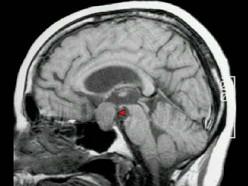

问题 男,37岁,视力模糊,部分视野缺失,伴有头痛、恶心数月,MRI检查如图,最可能的诊断为()

选项 A.颅咽管瘤 B.脑膜瘤 C.蛛网膜囊肿 D.垂体瘤 E.表皮样囊肿

答案 D